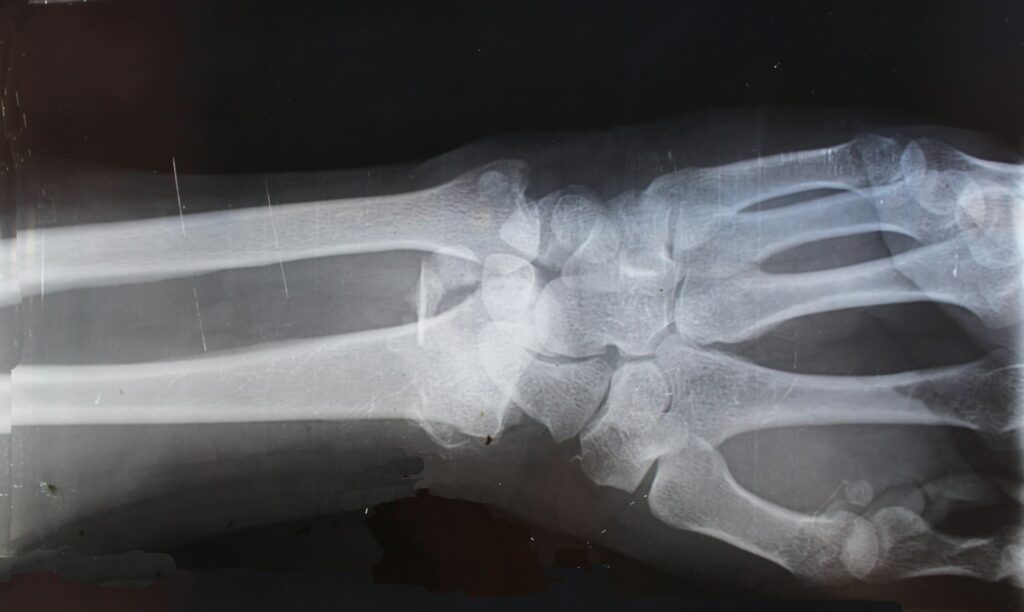

Seúl, 14 de septiembre de 2025. — Un equipo de investigadores de la Universidad Sungkyunkwan (SKKU), en Corea del Sur, ha desarrollado un dispositivo que parece sacado de la ciencia ficción: una pistola de pegamento modificada capaz de imprimir injertos óseos biodegradables directamente sobre fracturas durante una cirugía. La innovación, publicada en la revista Device, podría transformar la traumatología al permitir implantes personalizados en tiempo real, más baratos y con menor riesgo de infección.

En pruebas con modelos animales (conejos con defectos femorales graves), los injertos impresos con esta pistola mostraron resultados superiores al cemento óseo comercial, el material más habitual en quirófanos ortopédicos: